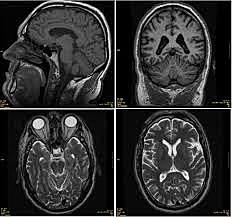

P. Mansfield desarrolló las secuencias EPI. R. C. Hawkes y Moore et al en 1980 obtuvieron las primeras imágenes de la cabeza

en 1981 se instaló el primer prototipo de tomógrafo por RM en el Hospital Hammersmith de Londres, dando inicio a los estudios pioneros de Graeme M. Vides, Ian R. Young en el departamento dirigido por el profesor Robert E Steiner.

. P. Mansfield y P. Lauterbur fueron galardonados con el premio Nobel de Fisiología y Medicina de 2003.